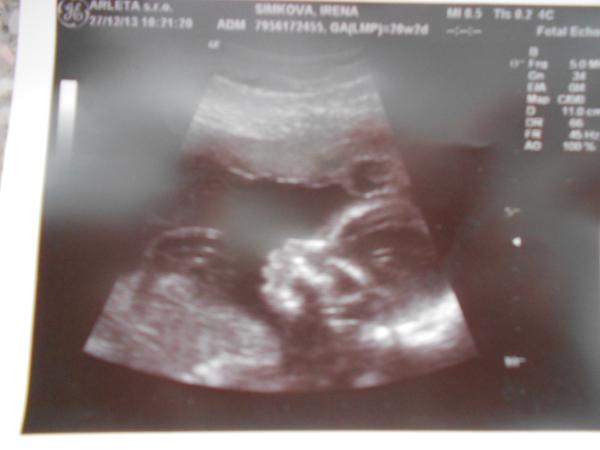

Ahoj holky, i já se přidávám, pozdě ale přeci. Krásný rok 2014, ať tu pokračuje náš super trend těhu vlny a mi co už těhu jsme, ať to zdárně dotáhneme do porodnice a máme hladký pohodový porod 😎 . Jinak prďolka se minulý pátek nechtěl ukázat, tak pořád nevíme co to bude. Další UZ v lednu, tak snad už se stydlín ukáže. Jinak má 12 cm od hlavy k prdelce, celý asi 16 cm. To už je kus člověka, ne? 😀